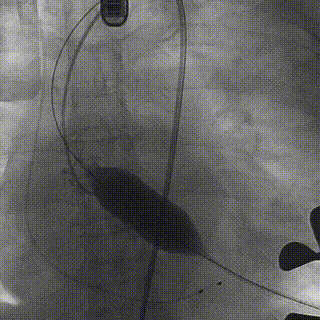

释放瓣膜:瓣膜释放后造影确认发现左冠窦侧定位件将左冠瓣叶牢牢束缚在支架瓣膜上,让冠脉开口有更大的空间,团队决定行后扩张,以保证有更加完美的瓣膜形态和血流动力学。

再次以25mm球囊扩张后复查根部造影,瓣周未见明显反流,冠脉显影良好,超声复查,主动脉瓣无瓣周漏,前向流速1.8m/s,二尖瓣反流也较术前明显减少。